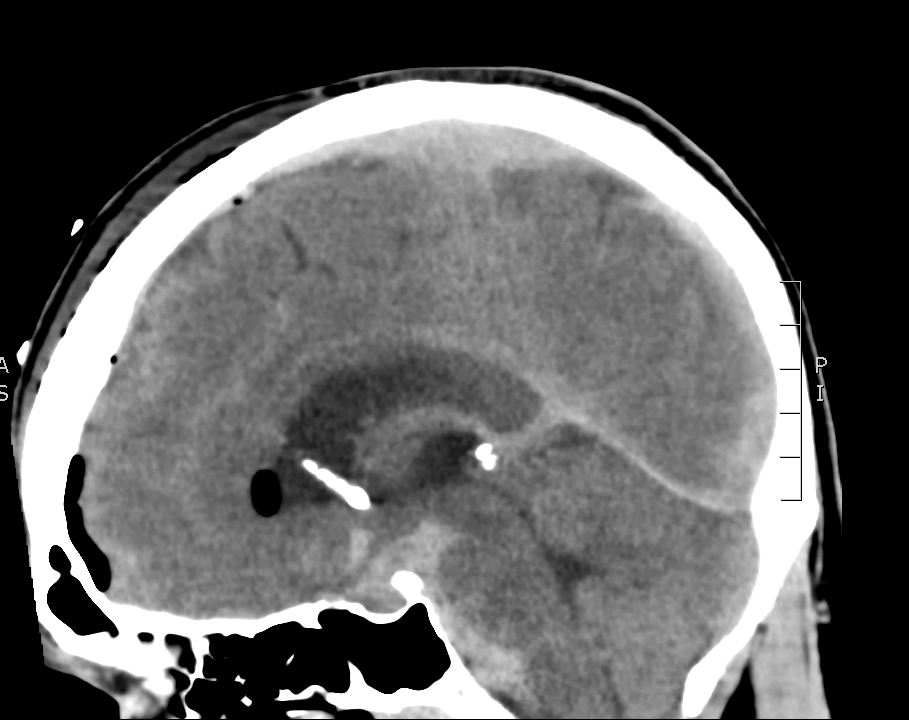

There is a lot going on in this CT – but you may have realized that there is diffuse subarachnoid hemorrhage. There are a number of other findings that we’ll walk through. First, take a look at using our coronal and sagittal views – fun fact, these are simply computer reformats of the axial above.

Coronal CT

If you go back to the coronal and sagittal images you can try to find the same structures. You’ll also see that there is a fair amount of subarachnoid hemorrhage anterior to the brain stem.